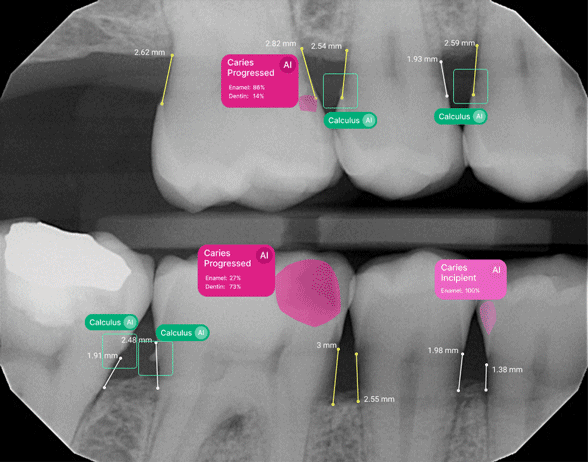

We know... AI dental innovation sounds high-tech (and maybe even a little intimidating). But honestly, it’s one of the most helpful tools we’ve added in recent years.

With AI-assisted dental technology, we’re able to analyze your scans with incredible precision. That helps us catch issues early, plan cosmetic treatments more effectively, and make sure everything fits just the way it should.